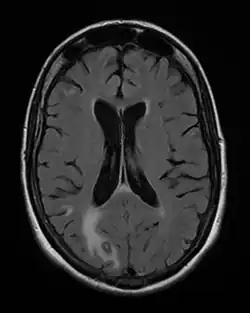

Lymph nodes affected by Toxoplasma have characteristic changes, including poorly demarcated reactive germinal centers, clusters of monocytoid B cells, and scattered epithelioid histiocytes.

- ^ CNS Toxoplasmosis Imaging at eMedicine